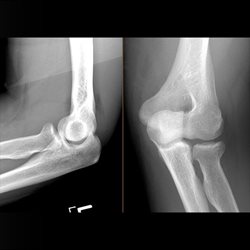

Various adult extremity cases. Shoulder, wrist, ankle, elbow.